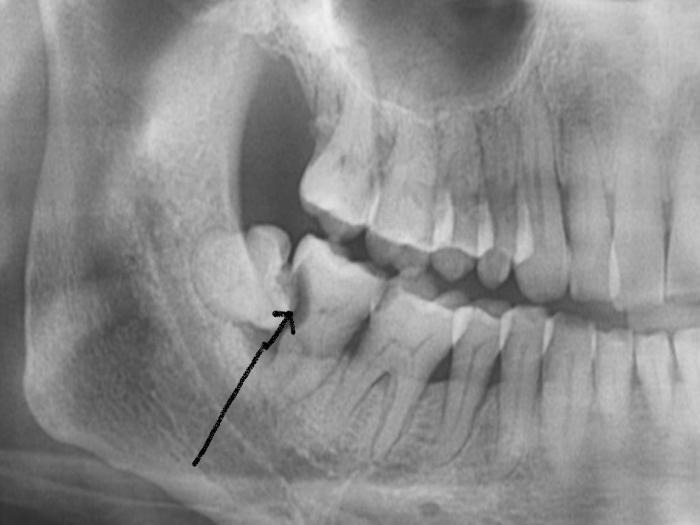

智齿在作怪。智齿是最容易塞的一颗牙了,因为大多数人智齿长得都不正,别的牙都是从下往上竖着长,可智齿经常从后往前横着长,于是它跟前面的牙之间就出现了一道楔形的沟,这样就极其容易塞牙。